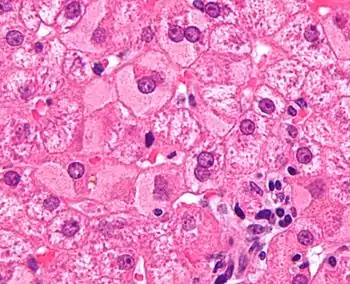

Мікрофотографія що показує матово-склоподібні гепатоцити

Матово-склоподібні гепатоцити (англ. ground glass hepatocyte), GGH) — це патологічні клітини паренхіми печінки з імлистим і рівномірно тьмяним виглядом цитоплазми при світловій мікроскопії. Рівномірне еозинофільне забарвлення цитоплазми спричинене присутністю HBsAg.

Цей вигляд зазвичай пов'язують з великою кількістю антигену гепатиту B у ендоплазматичному ретикулумі, хоча також може спричинюватись і ліками.[1][2] В контексті гепатиту B, матово-склоподібні гепатоцити спостерігаються лише при хронічній інфекції, і не спостерігались при гострій.